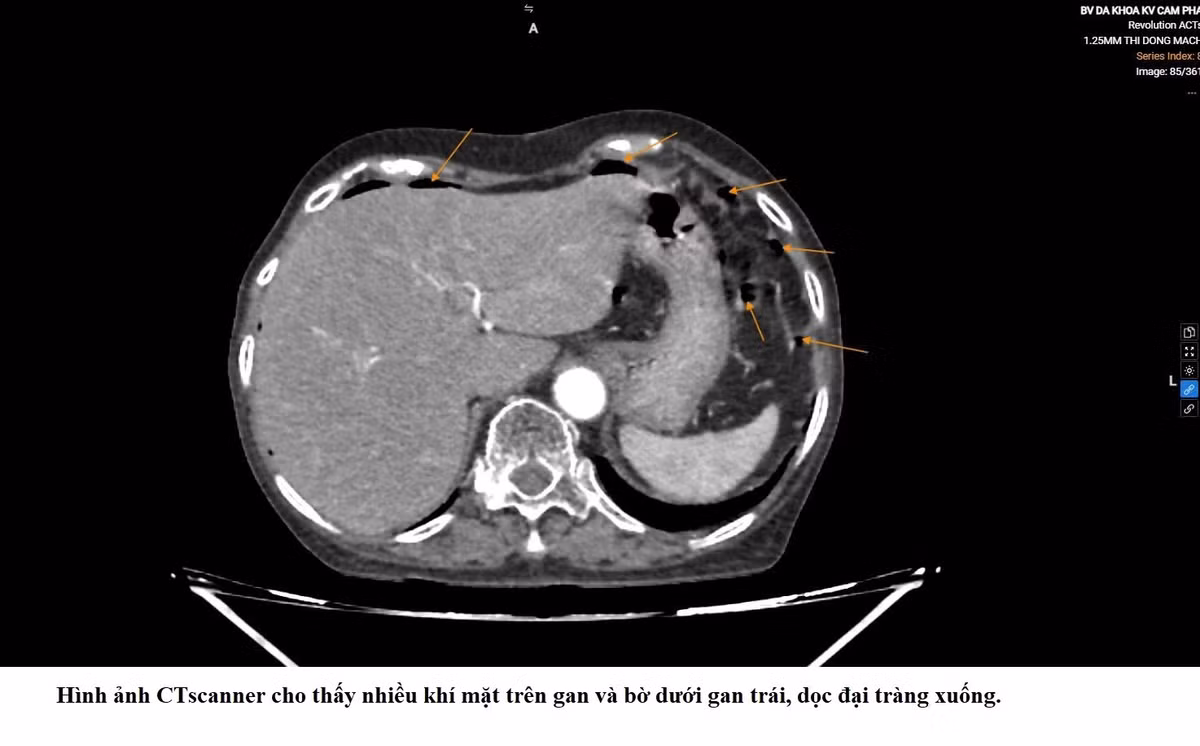

Qua thăm khám và các xét nghiệm cận lâm sàng, các bác sĩ xác định bệnh nhân bị viêm phúc mạc do thủng đại tràng trái và nhanh chóng chỉ định phẫu thuật nội soi cấp cứu.

thung-tang.jpg

Biểu hiện của thủng tạng rỗng trên phim chụp - Ảnh BVCC